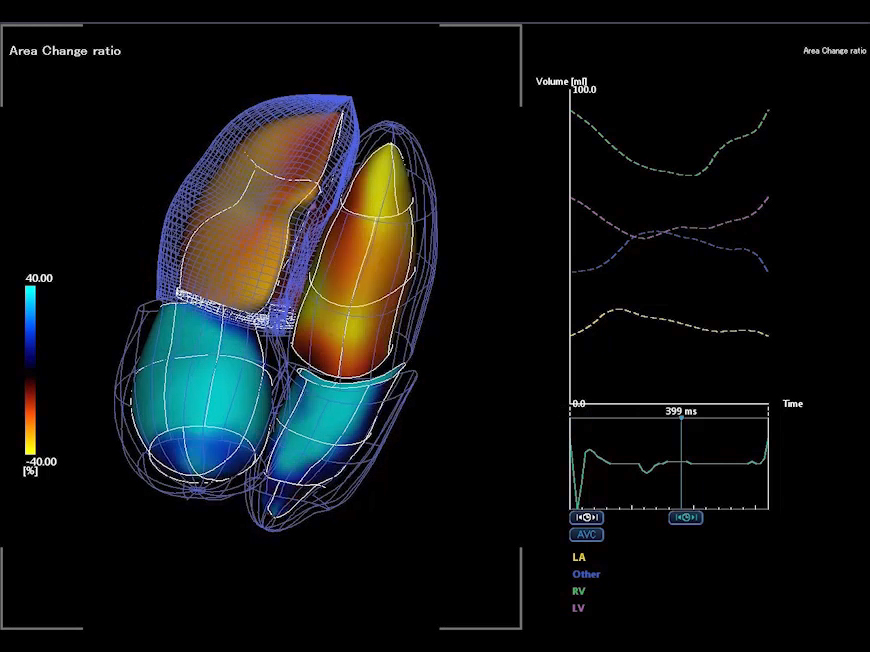

Auto-EF with Global Longitudinal Strain (GLS)1

- Automatic integration of Strain measurements with Ejection Fraction and volume measurements

- No need to enter dedicated strain packages

- Aplio systems automatically calculate Ejection Fraction, LV volumes and now GLS.

- Auto EF with Full-assist function is powered by artificial intelligence2

1Available on Aplio i-series / Prism Edition and a-series

2Available on Aplio i-series / Prism Edition

Automatic integration of Strain measurements with Ejection Fraction and volume measurements without the need of dedicated strain packages.

Advanced wall motion tracking technology.

3D Wall Motion Tracking*

The Aplio i900’s advanced 2D and 3D Wall Motion Tracking technology provides visual and quantitative access to global and regional myocardial wall motion dynamics.

*Available on the Aplio i900 only.

Tracking of multiple cardiac chambers.

Quad-Chamber Tracking*

Quad-Chamber Tracking displays the tracking of multiple cardiac chambers in one view along with waveforms.

*Available on the Aplio i900 only.